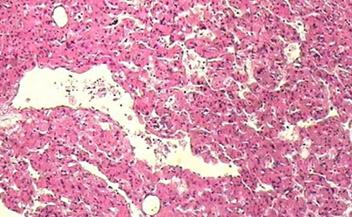

肾错构瘤,是最常见的肾脏良性肿瘤。因为在显微镜下看到的主要成分有:血管、平滑肌及脂肪组成,所以也称 肾血管平滑肌脂肪瘤。

错构瘤中血管、平滑肌、脂肪成分含量因人而异